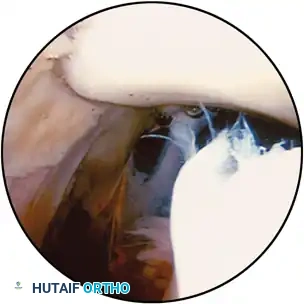

Suprapatellar Pouch and Patellofemoral Joint With the arthroscope in the distended suprapatellar pouch and the knee in extension, the surgeon systematically examines the synovium, patella, trochlear notch of the femur, synovial plicae, adhesions, and quadriceps tendon. With the oblique forelens of the arthroscope directed superiorly, the undersurface of the quadriceps tendon can be inspected. The synovium usually is quite thin in this area. By rotating the arthroscopic lens alternately to the right and left, the synovium, suprapatellar plicae, adhesions, and other structures within the superior part of the pouch can be seen. The character of the synovial villi, their vascularity, signs of infl ammation, and crystalline deposition can be evaluated. Suprapatellar plicae and mild adhesions rarely are of pathological importance. By sweeping the arthroscope from side to side and by moving it inward and outward, one can focus carefully on the individual structures. By slowly withdrawing the arthroscope with the forelens looking upward, the undersurface of the patella can be examined (Fig. 48-7A). With the suprapatellar pouch maximally distended and the knee in full extension, the arthroscope can sweep across the patellofemoral joint easily. The central ridge and medial and lateral facets of the patella are carefully inspected. Manipulation of the patella, depressing or tilting each edge, allows inspection of its entire articular surface, the condition of which should be noted. Rotating the lens so that it is facing inferiorly allows similar inspection of the surface of the trochlear notch of the femur. The congruity of the patella in the patellofemoral joint and its dynamics in fl exion and extension are best viewed from a superolateral portal. If a superomedial portal has been made for infl ow, the outfl ow can be switched to one of the anterior portals, and the scope can be passed down the previously placed superomedial infl ow cannula. Patellar tracking and congruency also can be evaluated from the anterolateral portal with the scope withdrawn distal to the inferior pole of the patella and turned toward the patella (Fig. 48-7B). The arthroscope is rotated to point toward the medial peripatellar region. In about 40% of knees, a medial synovial plica running slightly medial and distal to the patella can be identifi ed (Fig. 48-7C). This synovial and fi brous band usually originates medially from the side wall of the suprapatellar bursa and inserts into the fat pad distally. It may be responsible for anterior knee pain, popping, and chondromalacic changes on the medial femoral condyle when it is thickened and fi brotic from trauma or chronic synovitis. Occasionally, a large medial plica impedes the sweep of the arthroscope inferiorly toward the medial compartment. If this occurs, the arthroscope must be partially withdrawn so that it is disengaged from the plica.

Fig. 48-7 A, Suprapatellar pouch with view of undersurface of articularis genu. B, Tangential view of patellofemoral articulation. C, Normal medial parapatellar plica. D, Posteromedial compartment is seen by passing arthroscope through intercondylar notch after viewing medial compartment. E, Posteromedial compartment is seen through posteromedial portal, which is made after completion of routine examination if complete posteromedial view is unsatisfactory. F, Medial meniscus and medial compartment. G, Cruciate ligaments with fatty synovium covering posterior cruciate ligament. H, View of lateral meniscus and lateral compartment. I, View of posterior horn of lateral meniscus and popliteal tendon through hiatus. J, Posterolateral view of knee with arthroscope in anterolateral portal showing popliteal tendon insertion into femur in popliteal hiatus. in 10 to 30 degrees of fl exion, a valgus stress is applied, and the tibia is externally rotated. For a systematic examination of the medial meniscus, the meniscus is divided into regions—posterior, middle, and anterior thirds. The arthroscope is allowed to slip between the medial femoral condyle and medial tibial plateau articular surfaces. It should be allowed to slide into a space that has been previously opened up by applying stress to the joint. The arthroscope should never be forced between the condyles because severe scuffi ng and gouging may result. The arthroscope should be retracted from between the articular surfaces before releasing any of the stress. If the stress is released fi rst, the sharp edge at the tip of the arthroscope would gouge the articular surface as the arthroscope is retracted. The lens is directed anteriorly to view the anteromedial capsule, while establishing the anteromedial portal. The anteromedial portal is located 1 cm superior to the medial joint line and 1 cm medial to the border of the patellar tendon. Under arthroscopic observation, an 18-gauge spinal needle can be inserted through the planned portal site, and satisfactory position is confi rmed. The spinal needle should be free of the fat pad and safely superior to the medial meniscus. Under arthroscopic observation, the needle can be passed into the medial compartment to ensure that it has the proper location and plane to pass between the medial femoral condyle and tibial plateau. The needle is removed, and a skin incision is made with a No. 11 blade. With the arthroscope, the tip of the knife blade can be observed as the portal is created, protecting the articular cartilage of the medial femoral condyle. A probe is inserted through this portal. With the lens directed posteriorly, the inner free edge of the posterior third of the medial meniscus can be viewed from its intercondylar tibial attachment to the posteromedial corner of the knee (Fig. 48-7D). Only in a lax knee can the posterior meniscosynovial and capsular attachments be viewed from this anterolateral portal. Examination of the meniscus is made easier by inserting a probe through an anteromedial portal. The probe is used to lift, to depress, or to retract the meniscus gently. Frequently, tears through the surface of the meniscus, not noted by simple visual inspection, can be shown by probing. Examination of the meniscus is never complete until the entire meniscus is probed. The instrument should be used gently for this because the meniscus can be torn by too vigorous probing, especially when the tip of the probe is used. The posterior horn of the meniscus should be viewed with the knee fl exed (10 to 30 degrees) and externally rotated and by internally and externally rotating the tibia on the femur. If a small rim of the medial meniscus is seen instead of a meniscus of normal size, the knee may have had a prior medial meniscectomy or a displaced bucket-handle tear of the medial meniscus, with a major portion of meniscus displaced into the intercondylar notch or a meniscal fl ap behind the femoral condyle or rolled under the intact portion of the meniscus. Often a torn, displaced meniscus in the intercondylar notch fi lls the space between the medial femoral condyle and tibial plateau anteriorly, blocking the arthroscope’s access to the medial compartment. Peripheral detachments of the medial meniscus, although not directly viewed, may be suspected if abnormal meniscal movements are present, such as wrinkling. Viewing of the peripheral portion of the posterior third of the medial meniscus and its attachments usually can best be accomplished through a posteromedial portal or with a 70-degree angled arthroscope passed through the intercondylar notch and into the posteromedial compartment (Fig. 48-7E). The arthroscope should be withdrawn slightly and the lens rotated directly medially to view the middle third of the medial meniscus. The superior and inferior surfaces and the stability of the meniscus should be observed under probing. The meniscosynovial refl ection at the periphery, the synovial covering, and the midmedial capsular and posterior oblique portions of the medial collateral ligament complex (Fig. 48-8) should be evaluated. The peripheral attachment of the middle third of the medial meniscus can be seen clearly. The arthroscope can be moved back into the anteromedial compartment and the lens rotated further anteriorly to examine the anterior horn of the meniscus. The fat pad may obliterate the view of its most anterior portion. Further distention of the knee by closing the irrigation outfl ow may push the fat pad away a few millimeters so that this area can be viewed. If viewing still is impossible, redirecting the arthroscope, inserting a probe through an anteromedial portal to retract the fat pad, resecting a portion of the fat pad, or moving the arthroscope to a midpatellar portal may allow viewing of this area. The articular surfaces of the femoral and tibial condyles should be examined systematically for defects indicating chondromalacia or other abnormalities. Flexing the knee